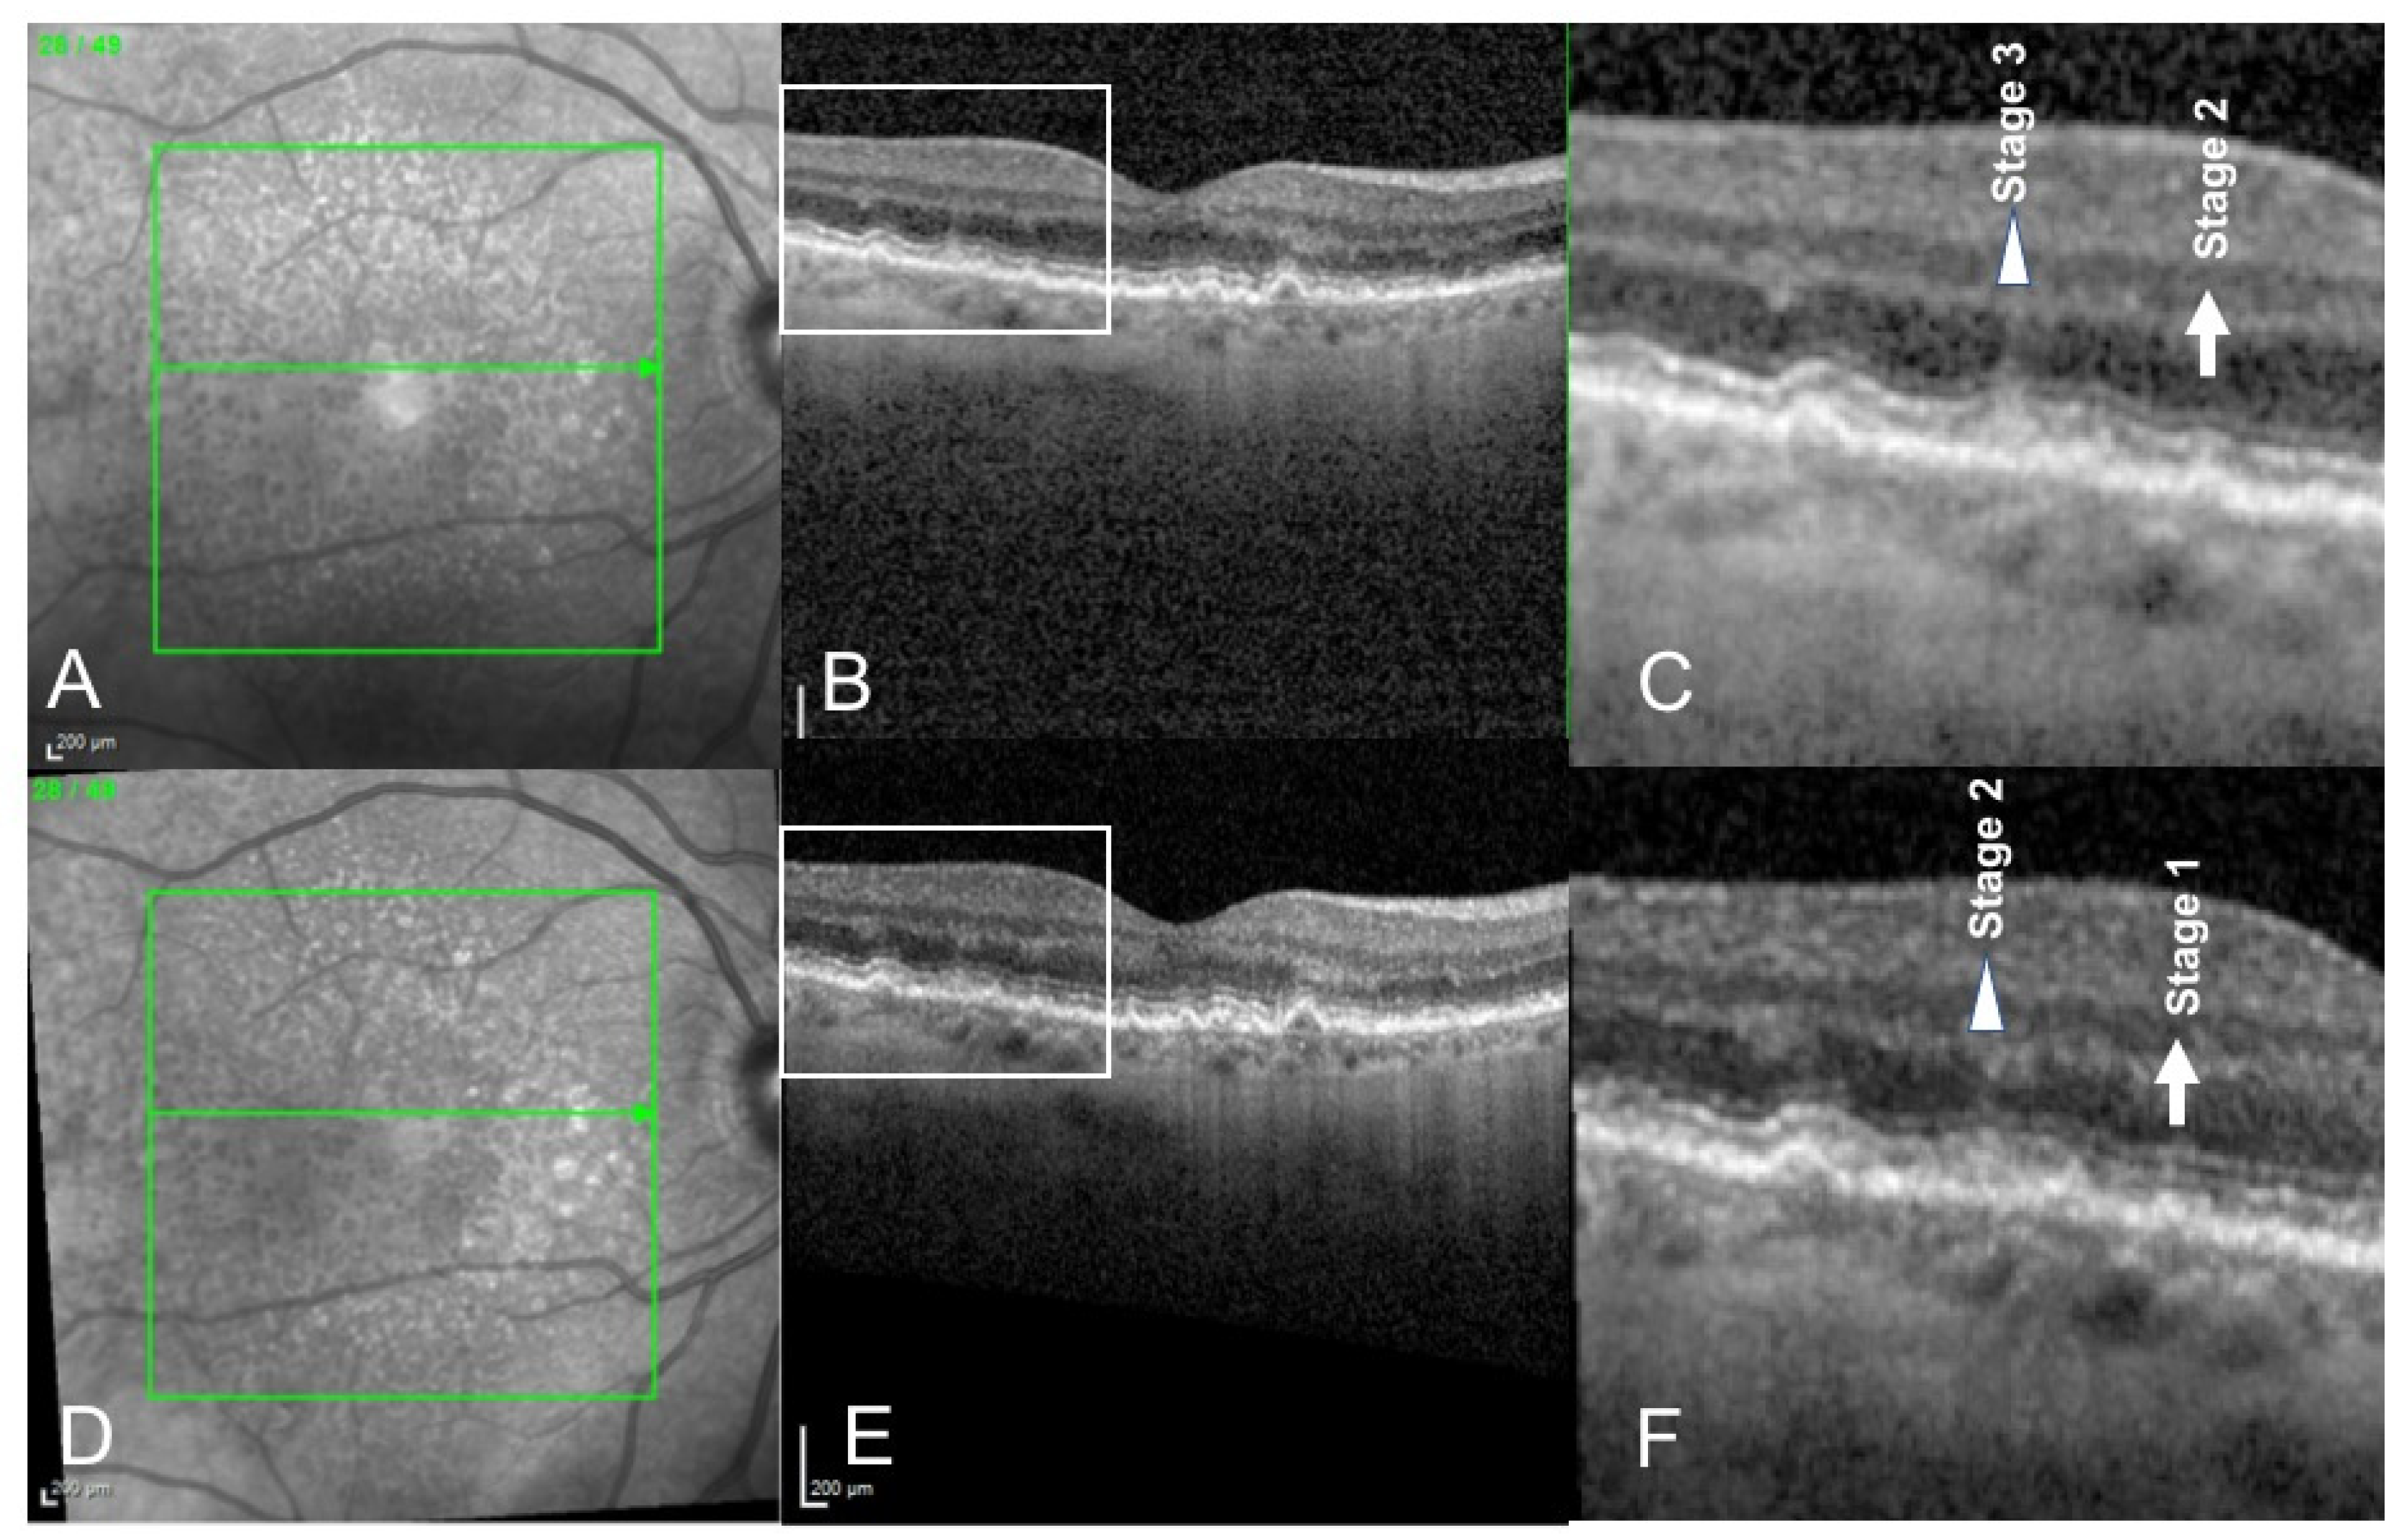

- Querques, G.; Canoui-Poitrine, F.; Coscas, F.; Massamba, N.; Querques, L.; Mimoun, G.; Bandello, F.; Souied, E.H. Analysis of Progression of Reticular Pseudodrusen by Spectral Domain–Optical Coherence Tomography. Investig. Ophthalmol. Vis. Sci. 2012, 53, 1264–1270. [Google Scholar] [CrossRef] [PubMed]